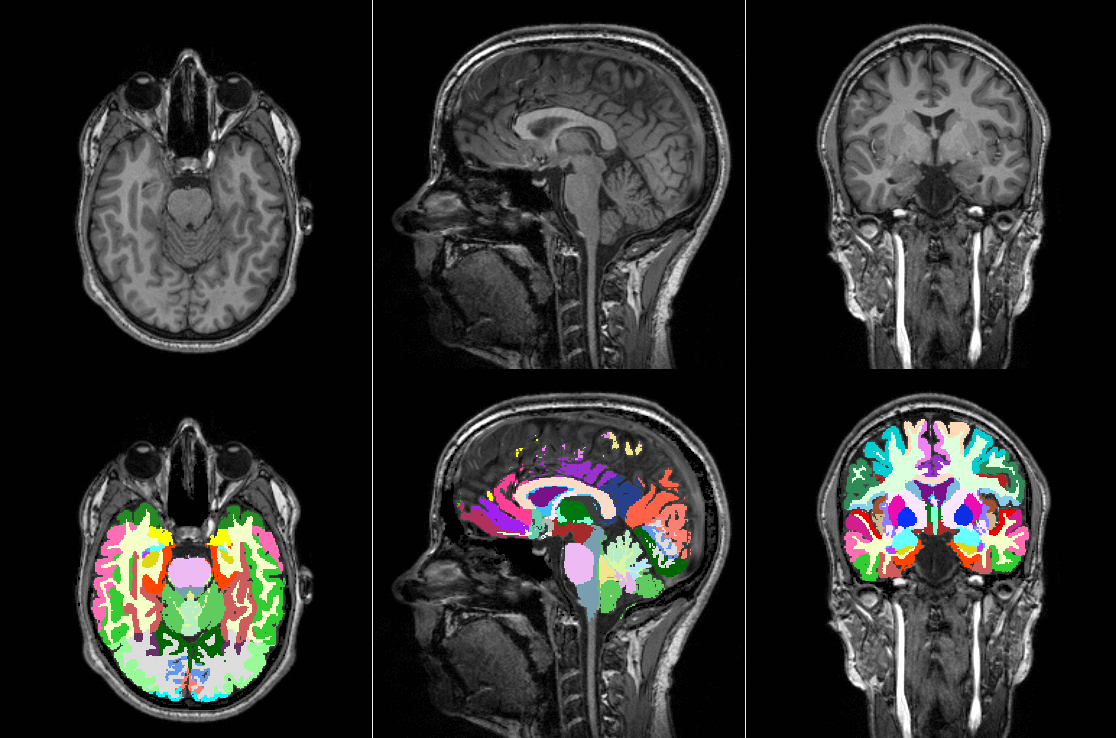

>>> subject = tio.datasets.Colin27()